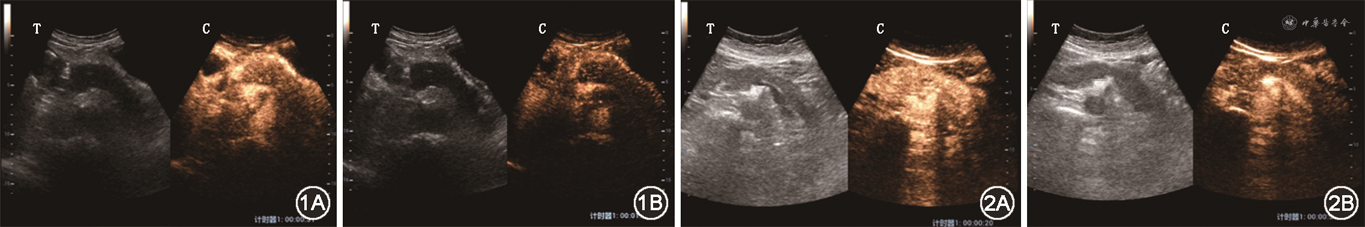

3. 治疗前首次就诊时胰腺超声造影表现:(1)17例胰腺弥漫性受累者中,有9例胰腺整体在增强早期、增强晚期、延迟期依次表现为稍低增强-低增强-低增强(图1),有5例在增强早期、增强晚期、延迟期依次表现为等增强-低增强-低增强(图2),有3例在增强早期、增强晚期、延迟期依次表现为稍高增强-低增强-低增强;(2)37例胰腺局灶性受累者中,有25例病灶在增强早期、增强晚期、延迟期均表现为低增强-低增强-低增强(图3),7例在增强早期、增强晚期、延迟期均表现为等增强-等增强-等增强(图4),2例在增强早期、增强晚期、延迟期依次表现为稍高增强-低增强-低增强,3例在增强早期、增强晚期、延迟期依次表现为稍高增强-等增强-等增强。

17例胰腺弥漫性受累者中:(1)共有8例患者治疗后在增强早期-增强晚期-延迟期3期中至少有1期出现了造影强度的增高:其中有5例患者胰腺整体的增强模式由治疗前的稍低增强-低增强-低增强变为治疗后的高增强-稍低增强-稍低增强(图5),2例由治疗前的稍低增强-低增强-低增强变为治疗后的等增强-低增强-低增强,1例由治疗前的等增强-低增强-低增强变为治疗后的等增强-等增强-等增强;(2)共有2例患者在治疗后出现了造影强度的减低:由治疗前的稍低增强-低增强-低增强变为治疗后的低增强-低增强-低增强;(3)共有7例患者在治疗前后造影强度没有发生变化,其中有4例在治疗前后均表现为等增强-低增强-低增强,3例在治疗前后均表现为稍高增强-低增强-低增强。